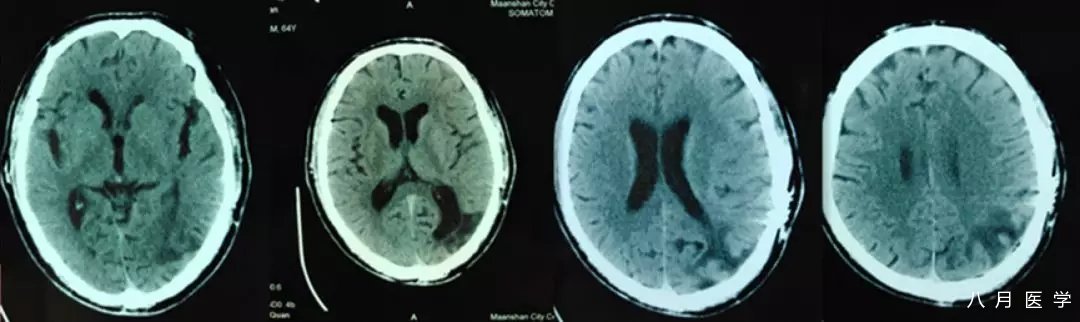

辅助检查:入院时急性头颅 CT 提示左侧枕颞叶软化灶。

24 小时后头颅 MRI 检查:左侧颞枕叶(DWI)未见明显急性病变,左侧大脑中/后动脉未见明显异常。